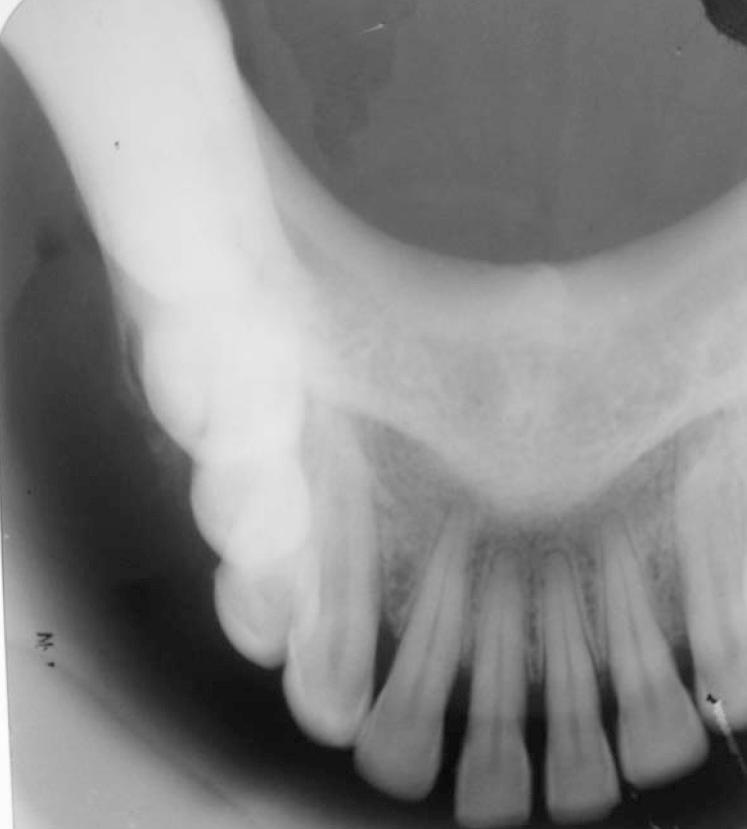

Osteosarcoma is a classical malignant bone-forming neoplasm which usually presents with an aggressive clinical course. The current case is presented with the radiographic feature of widening of the periodontal ligament space of the involved teeth, which is considered to be the earliest radiographic manifestation of osteosarcoma involving the jaw bone. The main aim of this case report was to focus on the importance of early diagnosis of this tumor based on clinical and radiographic examinations, and confirmation by histopathology. Considering the rarity of the disease type and particularly taking into account the fast progression and aggressiveness of this neoplasm, it is clear that the presentation of a clinical case represents a major contribution to better understanding of osteosarcomas involving the jaw bone.